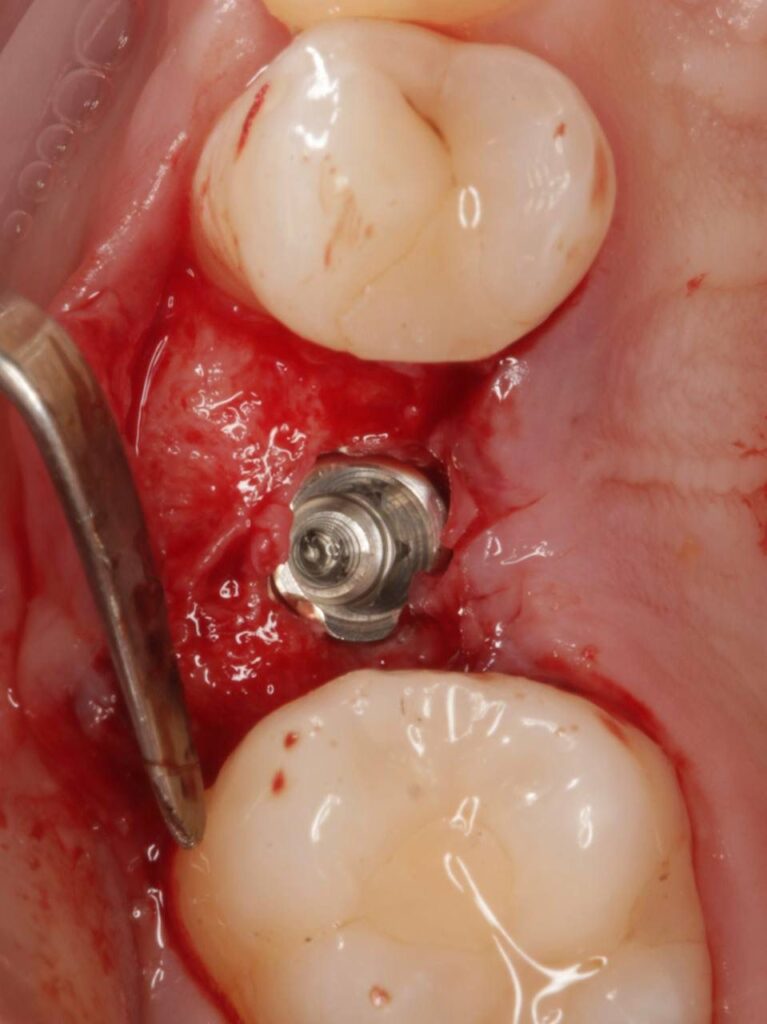

Специализация: терапия(эндодонтия), ортопедия, имплантология.